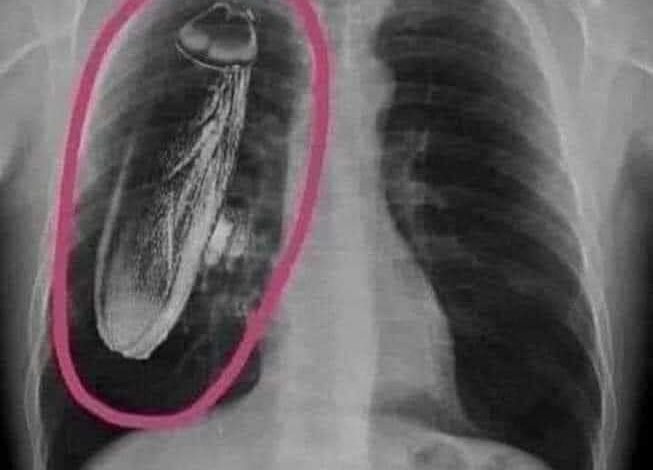

حالة نادرة جدًا.. ولادة #طفل يحمل توأمه داخل بطنه في #تونس وجد أطباء في تونس بعد الفحص لطفل مولود أنه ما زال يحمل شقيقه التوأم المتوفي داخل بطنه، وهي حالة تحدث لأول مرة في البلاد، وحدثت قبل ذلك ولكن يندر حدوثها في العالم وفق أطباء متخصصين في ذلك الشأن. وأكّد دكتور تخصص جراحة أطفال يدعى […]